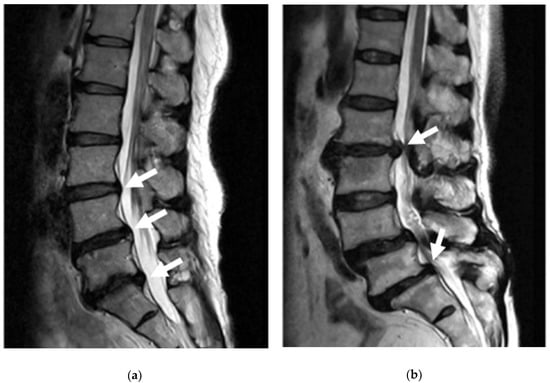

- Milette, P.C.; Fontaine, S.; Lepanto, L.; Cardinal, E.; Breton, G. Differentiating lumbar disc protrusions, disc bulges, and discs with normal contour but abnormal signal intensity. Magnetic resonance imaging with discographic correlations. Spine 1999, 24, 44–53. [Google Scholar] [CrossRef] [PubMed]

- Adams, M.A.; Hutton, W.C. Gradual disc prolapse. Spine 1985, 10, 524–531. [Google Scholar] [CrossRef] [PubMed]

- Kortelainen, P.; Puranen, J.; Koivisto, E.; Lahde, S. Symptoms and Signs of Sciatica and Their Relation to the Localization of the Lumbar-Disk Herniation. Spine 1985, 10, 88–92. [Google Scholar] [CrossRef]

- Frymoyer, J.W. Back Pain and Sciatica. N. Engl. J. Med. 1988, 318, 291–300. [Google Scholar] [CrossRef] [PubMed]

- Taher, F.; Essig, D.; Lebl, D.R.; Hughes, A.P.; Sama, A.A.; Cammisa, F.P.; Girardi, F.P. Lumbar Degenerative Disc Disease: Current and Future Concepts of Diagnosis and Management. Adv. Orthop. 2012, 2012, 970752. [Google Scholar] [CrossRef] [PubMed]